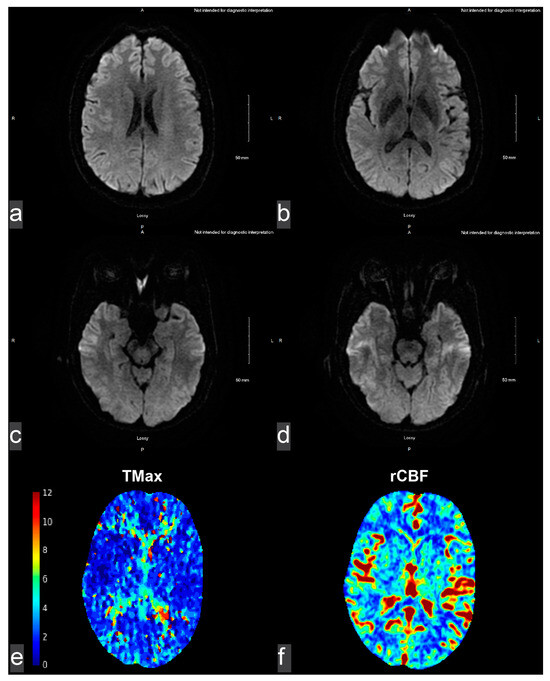

2. Detailed Case Description

2.1. Initial Presentation